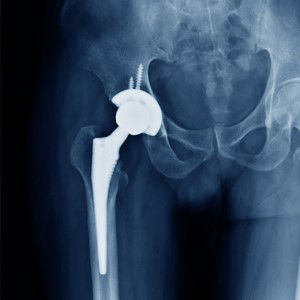

Kalça ProteziDiz Protezi